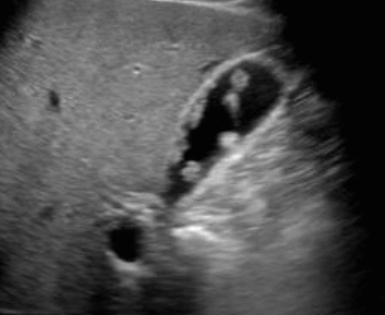

콜레스테롤 용종 (cholesterol polyp) 2. 선종성 용종 (adenomatous polyp) : 15~25%

- 대부분 단일성이다

- 1cm 이상일 경우 악성 가능성이 있다

- 콜레스테롤 용종보다 저에코 (hypoechoic)이다.

선종성 용종 (adenomatous polyp) 3. 염증성 용종 (inflammatory polyp) : 15%

- 만성 담낭염과 관련이 있다.